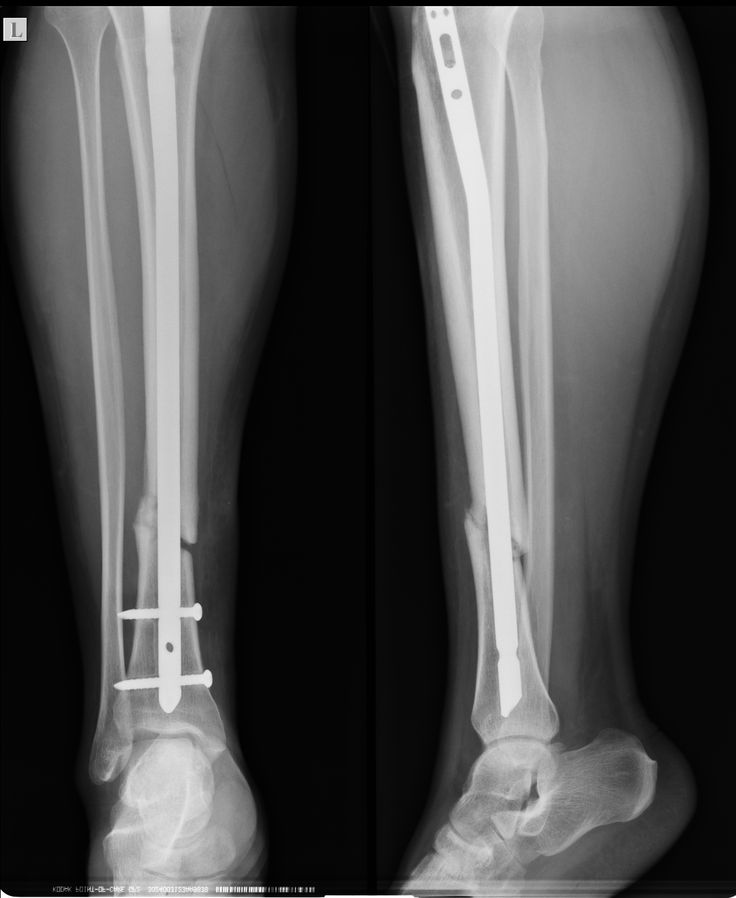

Intramedullary Nailing: Primarily for long bone fractures like the femur or tibia, using a rod inserted into the marrow canal to stabilize the bone.

Open Reduction and Internal Fixation (ORIF): “Open reduction” means the surgeon makes an incision to access the fracture, while “internal fixation” uses devices such as screws, plates, or rods to hold the bone fragments in place during healing.

Surgical Intervention: Displaced or complex fractures may require surgery to realign the bones and secure them with plates, screws, or rods.

Fracture Fixation: Broken bones may require surgical stabilization using plates, screws, or rods to realign and secure them.